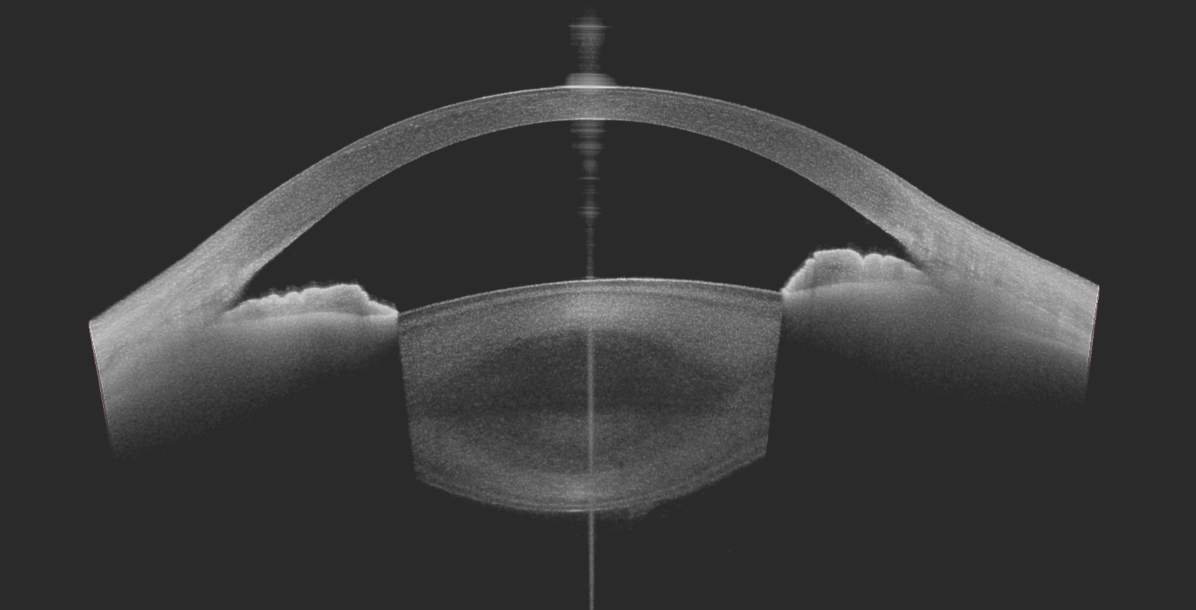

OCT SEGMENT ANTERIEUR

Tomographie à cohérence optique s'intéressant à la cornée et aux angle irido-cornéen.

Examen réalisé dans l'étude des anomalies de la cornée et de l'angle irido-cornéen.